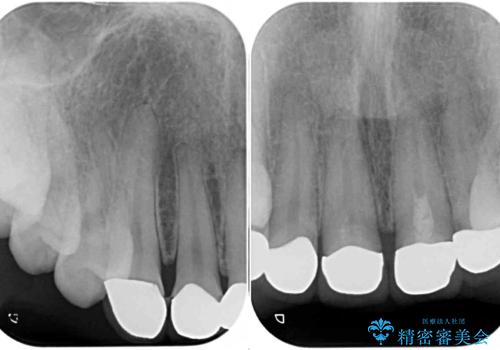

オールセラミッククラウン装着後、レントゲン写真より精度良く装着されていることは確認できているので、日頃のブラッシングで改善させるよう指導しています。